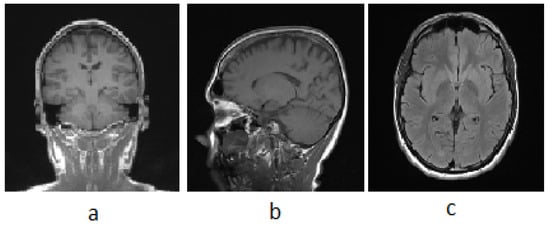

3.1. MRI